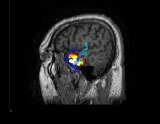

多模式神經(腦)影像、腦活動源精確定位、2D/3D影像,CURRY是功能非常強大的電磁溯源分析定位和可視化工具,該軟件在世界上處于最領先地位,推動了神經(腦)影像的飛速發展。

CURRY軟件包含多種功能,可以充分整合各種影像數據格式(EEG、MEG、MRI、fMRI、CT等)。通過將腦電活動與各種自發或功能影像數據的有機融合,CURRY為腦活動源的定位和分析提供了強有力的工具。CURRY可以利用MR和CT等得到的真實解剖結構影像,建立每個被試的顱骨和腦的3D模型(該模型對探明神經活動的發生源至關重要)。CURRY還可以將功能影像(如fMRI)和EEG、MEG的溯源重建進行比較,以增強結果的準確性。 CURRY可以在PC機、工作站、Laptops等運行,不僅可以用于研究工作(如腦的功能成像),而且,其強大的功能和先進性使其具有了更為廣泛的應用(如臨床、功能評估等)。

CURRY可以清晰地呈現具有高分辨率的各種影像及3D 重建結果(皮層、顱骨、頭皮、皮層斷層)。同時,可以觀察3D影像結果的動態變化(如3D Movie),具有很高的時間分辨率,也可以進行體積測量。